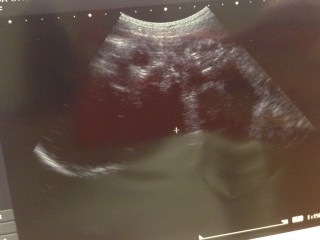

写真:36w2d:ゆかさん

2週間前から584gも増えて2684gでした。 2人目も女の子です。 手で顔を隠してて可愛かったです。 あと5日で正期産になります。 平成か令和になるのか楽しみです。 どっちでもいいから健康に産まれてきてね。 陣痛の痛み忘れたのでドキドキしてます。笑 NSTも採血も慣れました。 赤ちゃん元気に動いてて安心しました。 次から週1検診なので楽しみです。

36週2日2668グラム。 今日のお爺ちゃん先生は お顔のエコーも撮らず 口かず少ないので 物足りなさを感じますが、 2Dで目をこらして詳しく胎児を 診て下さるので、信頼しています。 大きく成長しますように♪

この週数にて転院と言うバタバタしい事になってましたが 担当の先生がエコーが上手いと聞いてて楽しみにしてたら 2dでこれだけ顔が見えました。 夫似かなー♥︎あと少しで会えるのが楽しみです!